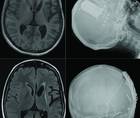

Utility of Stereoelectroencephalography in the Treatment of Drug-Resistant Epilepsy

Practical Neurology: Focus on Epilepsy & SeizuresUtility of Stereoelectroencephalography in the Treatment of Drug-Resistant Epilepsy